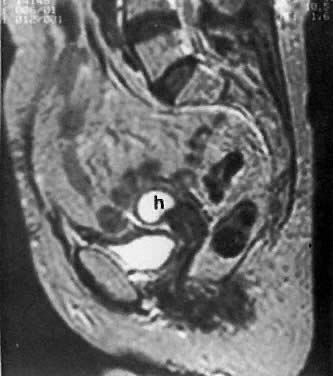

Fig. 10. Sagittal T2-weighted MRI of the pelvis shows moderate hydrometras ( h) caused by postirradiation cervical scarring.